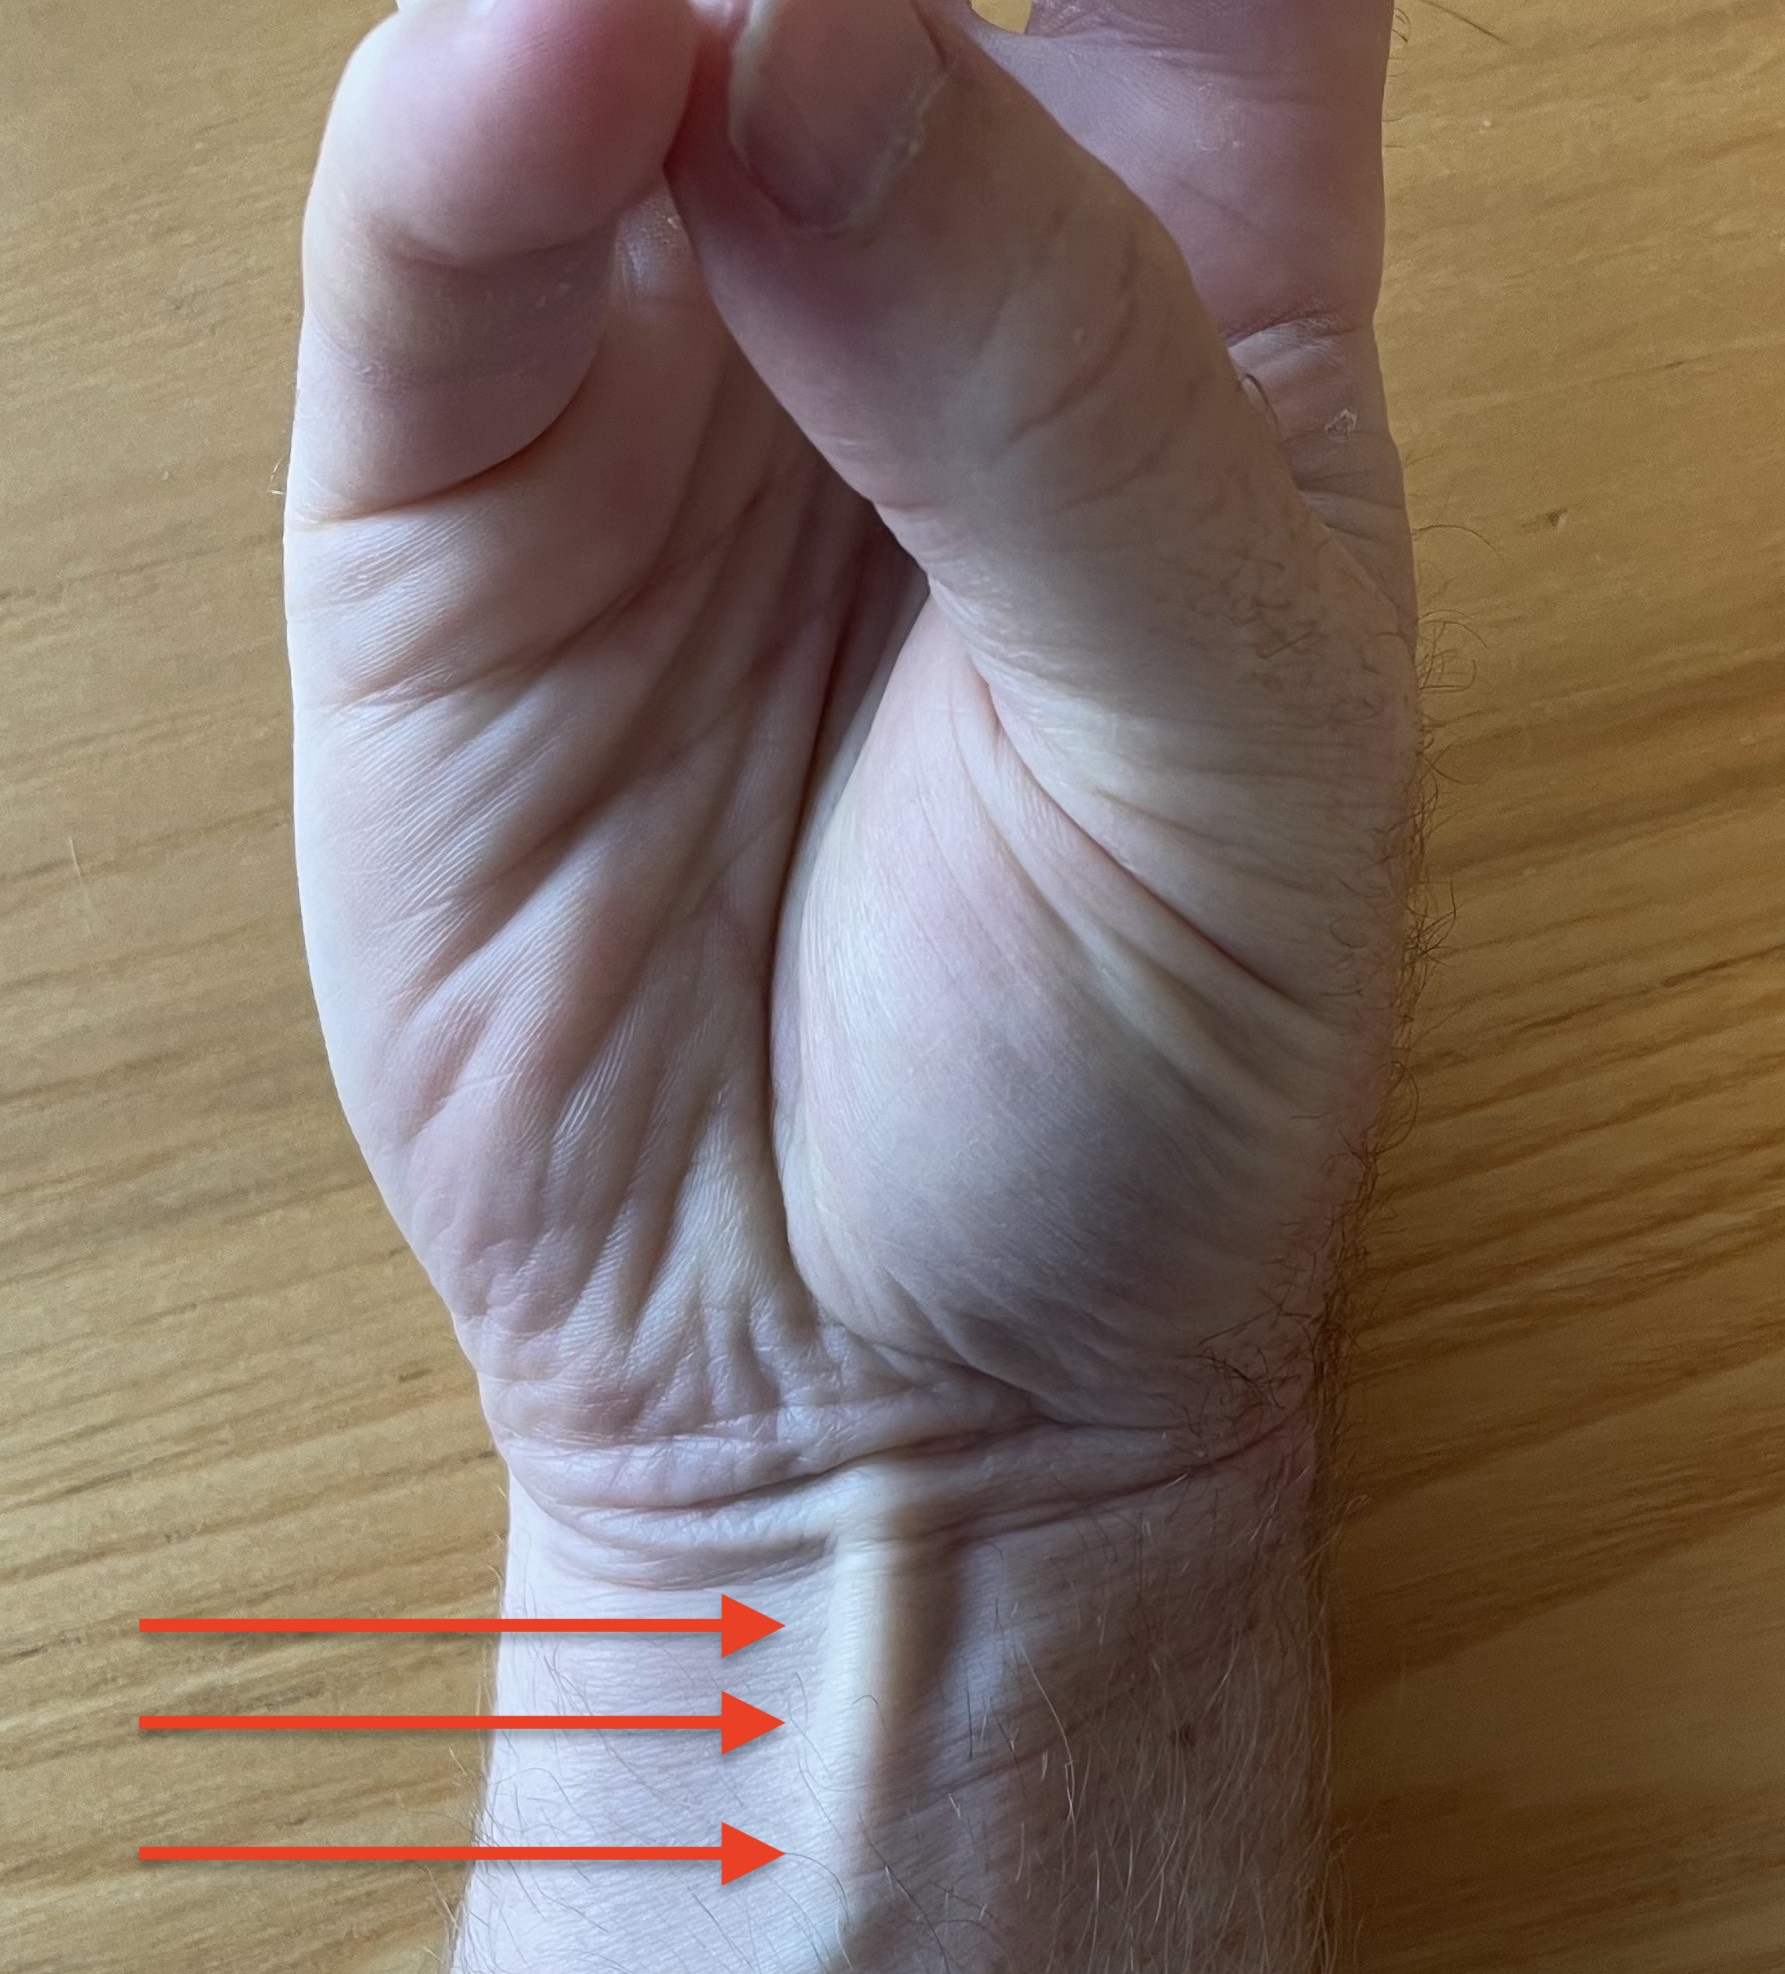

Palmaris longus - present 85% / press thumb and finger together